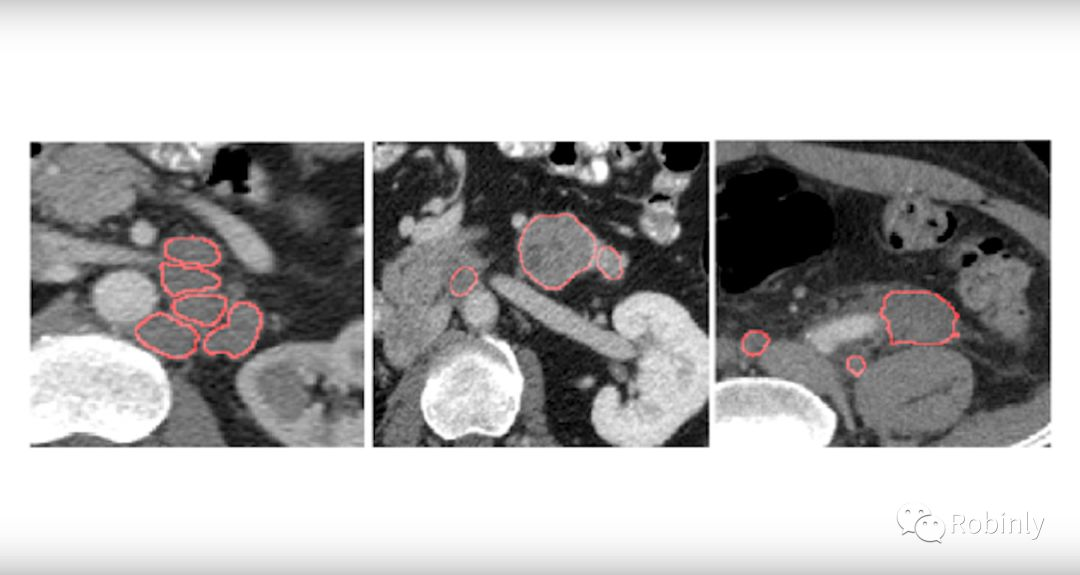

NIH研究的精确肿瘤测量工具。图片来源:NVIDIA Developer

在我看来,精准医学更可行,它对我们的实践影响更大,手段也更加直接。在美国最好的医院,医生通常接诊一名患者的时间是20-25分钟,在有限的时间内能达到的诊断和治疗手段不一定最佳方法,多借助计算机或计算应用会有很大的改进空间。比如用测量的肿瘤的大小作为例子,从理论上讲,测量体积会更好,但实际操作起来非常困难。因为人类医生没有时间在3维甚至4维图像中通过一个一个标注像素来计算肿瘤的体积,更不要说随着治疗的进行反复多次测量了。所以目前的手动处理方法并不理想。你需要在观察到的肿瘤放射影像切片中找到长得最大的切片,然后测量最长的直径,即所谓的长轴,再测量跟长轴垂直的短轴,再把这两个结果添加到患者的病例中来记录肿瘤的大小。但是这测量的只是面积的近似而不是3维体积,即便是同一个医生,下一次测量结果也可能有偏差。

医生非常擅长做复杂的抽象推理判断,这是目前机器学习无法做到的。即使到了今天,我们也没有为机器开发出这样的算法,我们的大脑太复杂和精细了。但是对于这种简单的测量,却是机器的长项,比人类的肉眼观察结果准确得多,可以作为精准医疗中的肿瘤测量手段。我们正在从事这方面的研究。例如检查、切割和测量淋巴结,胰腺,肿瘤等等的体积。